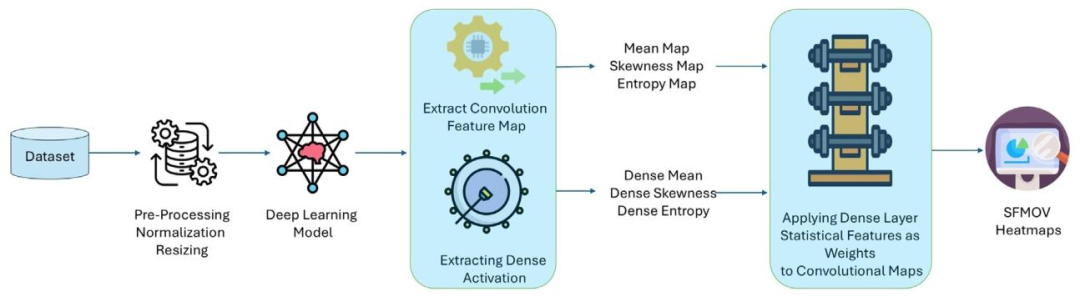

This work integrates rule-based modeling and visualizations withstatistical feature engineering and DL-based feature extraction to produce human-understandable explanations. This method bridges thegap between interpretable techniques’ transparency and black-box DLmodels’ predictive power. Fig. 1 shows an overview of the proposedmethod. First, some existing techniques are used in preprocessing, likedata augmentations, image resizing, and region of interest cropping.The resultant dataset is then fed into the custom MobileNetv2 DL modelfor feature extraction to capture complex visual patterns and get morediscriminative and informative deep features, which are crucial foraccurate classification. These extracted features are then used for statistical transformation to compute interpretable, summary-level insights.Next, a novel ZFMIS technique ranks and filters features based on theirinterpretive value. The filtered and selected features are then used totrain the decision tree and RuleFit interpretable rule-based models. Finally, Grad-CAM-inspired heatmaps (SFMOV) are generated to visualizethe most important statistical features and highlight spatial regions ofthe images that contribute significantly to the model’s decision-makingprocess. Visual overlays enhance statistical interpretation by illustrating how specific patterns affect categorization judgments, providingstakeholders with an intuitive understanding of the prediction model’sbehavior, a model-agnostic visual explanation technique.The pseudocode of the proposed methodology is presented in Algorithm 1. Each step is discussed in detail in the subsequent sections

本研究将基于规则的建模、可视化技术与统计特征工程及基于深度学习(DL)的特征提取相结合,生成人类可理解的解释。该方法填补了可解释技术的透明度与黑箱深度学习模型的预测能力之间的差距。图1展示了所提方法的整体框架:首先,采用一些现有技术进行预处理,如数据增强、图像 resize 和感兴趣区域裁剪;然后,将处理后的数据集输入定制的 MobileNetv2 深度学习模型进行特征提取,以捕捉复杂的视觉模式,获得更具判别性和信息量的深度特征——这些特征对准确分类至关重要;接着,利用这些提取的特征进行统计转换,计算可解释的、汇总级别的洞察;之后,一种新颖的 ZFMIS 技术根据特征的解释价值对其进行排序和筛选;再将经过筛选和选择的特征用于训练决策树和 RuleFit 这两种可解释的基于规则的模型;最后,生成受 Grad-CAM 启发的热图(SFMOV),以可视化最重要的统计特征,并突出对模型决策过程有显著影响的图像空间区域。视觉叠加通过说明特定模式如何影响分类判断,增强了统计解释的效果,为相关人员提供了对预测模型行为的直观理解,这是一种与模型无关的视觉解释技术。 所提方法的伪代码如算法1所示。后续章节将详细讨论每个步骤。

Fig. 1. Workflow of the proposed approach.

图1. 所提方法的工作流程。

Fig. 2. SFMOV process, extracting Mean, Skewness, and Entropy maps from convolutional features and dense layer activations, normalizing and combining them into a weightedheatmap overlaid on the input image.

图2. SFMOV流程:从卷积特征和密集层激活中提取均值图、偏度图和熵图,对其进行归一化处理后组合成加权热图,并叠加到输入图像上。